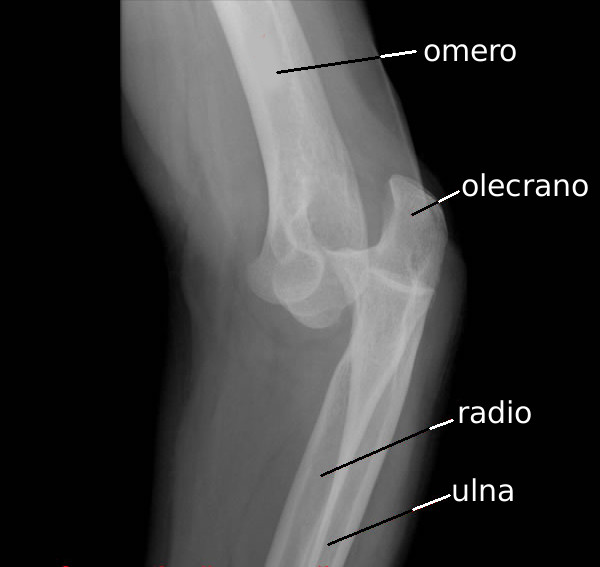

Lussazione

- Descrizione: Lesione di una articolazione nella quale le Ossa che la compongono escono dalla loro posizione normale.